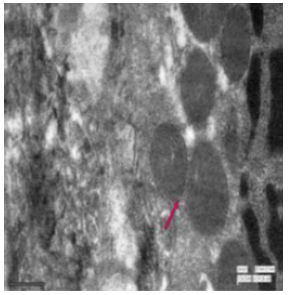

Transmission Electron Microscopic Changes

In the duodenum of the control rat, the enterocytes had a regular microvillus border, tiny finger-like projections and a few granular bodies (Figure 47). In the intranuclear region of the enteroendocrine cells, numerous tiny, electron-rich spheroidal granules were present (Figure 48). The microvilli were reduced in height and were damaged (Figure 49). The fluoridated duodenal mucosa had fat droplets suggesting lipid accumulation, vacuolations, a thickened epithelial membrane, multivesicular structures exhibiting endocytic activity and discernible widening of spaces (Figure 50). There were aberrant absorptive cells, granular bodies along mitochondria (Figure 51). The endoplasmic reticulum exhibited vacuolization. Goblet cells were seen among the cellular protrusions (Figure 52). The duodenal mucosa in fluoridated rats appeared flat with the absence of villi, indicating significant damage to the intestinal structure essential for nutrient absorption (Figure 53). Irregular nuclei along with some vacuolation were evident in fluorotic rats. (Figure 54). The jejunum in the control rat revealed normal mitochondria distinctly characterized by its outer membrane and well-developed cristae (Figure 55). Oval basal nuclei surrounded by nuclear membrane were visible in the cells. Several secretory granules and vesicles were present in the cytoplasm (Figure 56). Small intestinal crypts of Lieberkühn included Paneth cells, specialized epithelial cells. The nuclear membrane enclosing the basal nucleus were also seen (Figure 57).

Figure 55: Transmission electron micrograph of jejunum of control rat showing mitochondria (↑) with outer membrane and cristae. X 7000.

Figure 56: Transmission electron micrograph of jejunum of control rat showing nucleus surrounded by nuclear membrane (↑). The cytoplasm had secretory granules (↑) and vesicles. X 2550.

In the fluoride-treated rat, the endoplasmic reticulum had dilated cisternae, contained the virus particles, characterized by an electron-dense core enveloped by one or two membranes (Figure 58). Under the microvilli, a noticeable terminal web was seen and prominent lateral interdigitations were visible between the cells, suggesting complex folding or invaginations of cell membranes. Additionally, the mitochondria appeared swollen with few disintegrated cisternae (Figure 59). The jejunum of fluorotic rats displayed vacuolations. The presence of lysosomes and vesiculated RER was observed in the cytoplasm (Figure 60).

Figure 58: Transmission electron micrograph of jejunum of rat treated with 600 mg fluoride for 40 days showed virus particles (↑) having electron dense core surrounded by one or two membranes. X 5000.

Figure 59: Transmission electron micrograph of jejunum of rat treated with 600 mg fluoride showing interdigitations (↑) swollen mitochondria with few disintegrated cristae. Dilated reR (↑) was also seen. X 2550.

Figure 60: Transmission electron micrograph of jejunum of rat treated with 600 mg sodium fluoride showing vacoulations (↑), vesiculated reR (↑) and some lysosomes. X 2550.